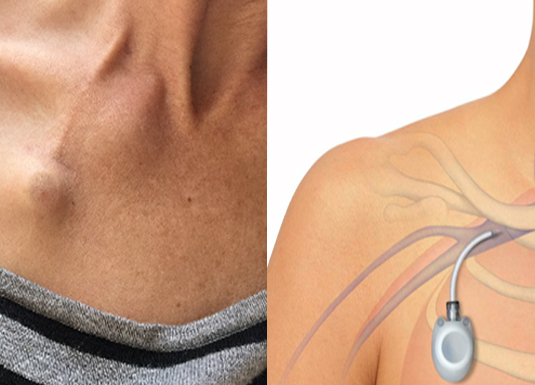

Central venous accesses:

Many of the tumors and some of the infections need long term administration of intra venous medicines. A peripheral line (commonly called as venous cannula) can be used for short term only, after which it gets displaced, blocked or infected and cannot be used further. A new cannula is secured each and every time these medicines are administered. Soon all the peripheral venous accesses are lost and further injections will not be possible. If long term venous access is anticipated placement of Chemoport and Hickman catheter is advisable to avoid a situation where all the peripheral veins will get exhausted. These also provide greater degree of comfort. Here a tube is placed with one end close to the heart. The other end exits through a long subcutaneous tunnel in the chest. This long tunnel offers stability and also protects from infection. Through the external end blood can be withdrawn for analysis and medicines can be administered. The external end of the tube could be buried beneath the skin as in Chemoport or could be hanging in the front of the chest. A peripherally inserted central venous catheter (PICC line) is a combination of both, wherein the line runs up a vein in the arm and ends in a large vein in the chest.